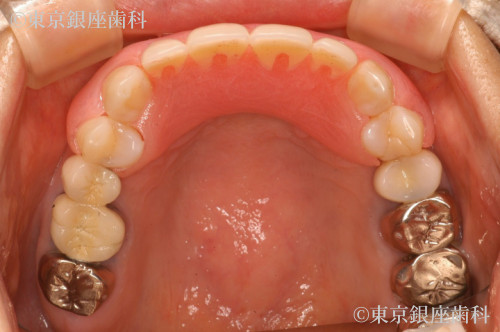

Before

After

前歯4本を入歯からインプラントに変更